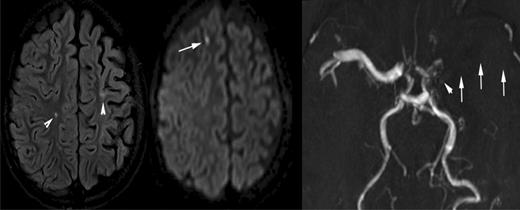

A 10-year-old boy with sickle cell disease and history of acute chest syndrome now presents with pain crisis. MRI of the brain was requested for episodic slurred speech. Axial FLAIR MR image (left) and DWI (middle) illustrate many of the manifestations of SCD in the brain. The arrowheads on the FLAIR image point out areas of old (silent) infarctions in the white matter of the centrum semiovale on the right and at the posterior aspect of the left superior frontal gyrus. The DWI shows an additional area of signal abnormality in the anterior aspect of the right superior frontal gyrus, representing a recent infarction. In addition, there is atrophy of the left cerebral hemisphere, which is seen in the setting of sickle cell–associated vasculopathy manifest by nonvisualization of the left middle cerebral artery by MRA (arrows on the right image). The MRA also shows subtle collaterals (moyamoya vessels) in the lenticulostriate distribution on the left (arrowhead).

In addition to the varying definitions of SCI, lesion detection is dependent on the magnetic resonance (MR) technique (fluid attenuation inversion recovery [FLAIR] or diffusion-weighted imaging [DWI], see Figure 3, vs traditional T2-weighted images), the slice thickness,11 and the magnetic field strength. As further advances in imaging are made and medical centers transition from 1.5 Tesla to 3.0 Tesla magnets, more individuals with SCA will be detected with SCI, and quantitative techniques are likely to detect subtle abnormality in those without SCI on T2-weighted MRI.12,13 Use of the greater magnet strength will most likely have an impact on measures of incidence and prevalence of SCI, especially in longitudinal studies and CNS-related clinical trials. Thus, investigators must consider the anticipated change in the magnetic strength of the scanner over time when conducting a longitudinal study.

As is required by this definition, children with SCI do not have any obvious evidence of symptoms, other than perhaps academic or behavioral difficulties. Quite often, the presence of SCI is detected when the child presents with subtle neurologic findings prompting a brain MRI. The neuroradiologist may identify additional previous infarcts and distinguish an acute cerebral infarct from a previously unknown SCI (Figure 3A). A focal DWI hyperintensity indicates an ischemic injury within the last 8 to 10 days14 (Figure 3B), while the presence of brain atrophy suggests a chronic process.